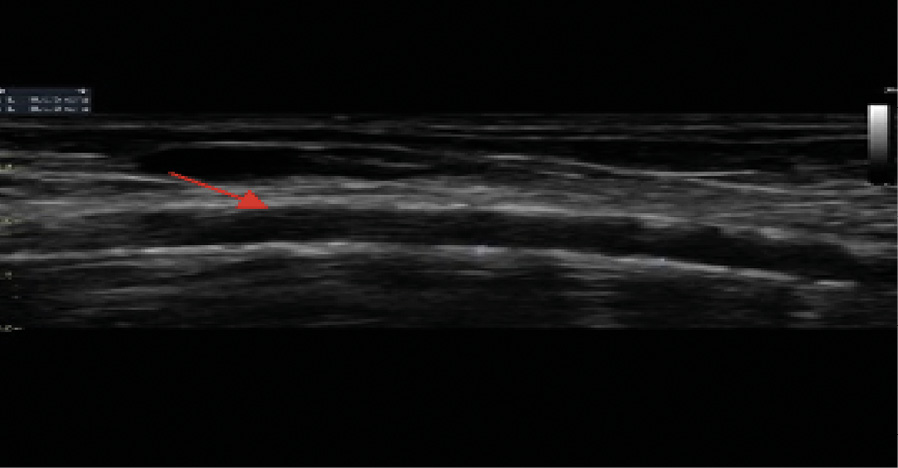

При ультразвуковом дуплексном сканировании артерий нижних конечностей в 2022 г. выявлен атеросклероз магистральных артерий нижних конечностей, эхографические признаки выраженного кальциноза магистральных артерий (рис. 4), окклюзирующий хронический тромбоз левой задней большеберцовой артерии в верхней и средней трети голени.

Рис. 4. Эхограмма пациента Т. Левая передняя большеберцовая артерия. Визуализируется диффузное относительно равномерное повышение эхогенности сосудистой стенки в сочетании с утратой дифференцировки на слои на всем протяжении (красная стрелка). Эхографические тени от повышенного содержания солей кальция фрагментарно перекрывают просвет и нижнюю стенку сосуда (желтые стрелки)